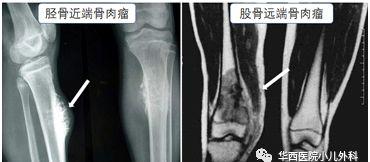

骨癌的专业名字叫恶性骨肿瘤,其中骨肉瘤是最常见的原发性恶性骨肿瘤,约占全部恶性骨肿瘤的1/3,主要出现在青少年身上,以10~25岁多见,发病部位多为股骨远端、胫骨近端及肱骨近端的干垢端。主要的表现是疼痛、肿胀。

在医院里,为了早期诊断、发现骨癌等恶性疾病,医生会根据娃儿的临床表现结合X光、MRI、血液等辅助检查进一步分析,并通过定期复诊等多重手段来判断是哪种腿杆痛。